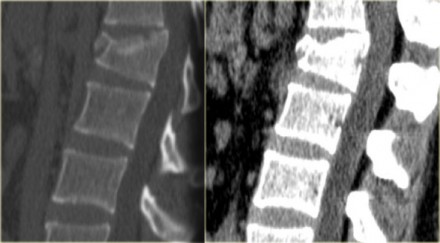

The sagittal reconstructions of the CT demonstrate that the posterior

part of the vertebral body is of normal height, but there is some

involvement of the posterior part of the vertebral body.

There is debate on how to treat these patients and if there is any role of MRI in these cases.

If you are aggressive you could call this a two column injury, which would require stabilizing surgery.

If you are conservative you could call this an injury with only minor involvement of the middle column.